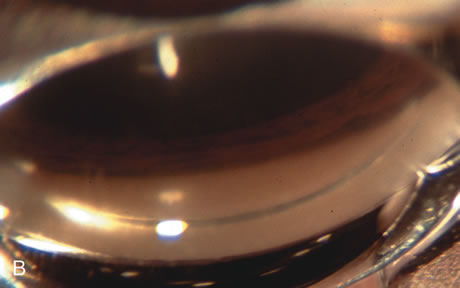

Fig. 3. Partial bleb failure following clear corneal phacoemulsification with foldable IOL. A. Preoperative bleb appearance prior to temporal lens extraction. Preoperative IOP was 12 mm Hg on no antiglaucoma medications. Time from 5-FU trabeculectomy surgery to lens extraction was one year. B. Bleb appearance 2 months after clear corneal cataract surgery with topical anesthesia. Following lens extraction, increased vascularity was noted along with decreased size of the filtering bleb. IOP increased to 20 mm Hg as early as 2 weeks after surgery, necessitating topical antiglaucoma therapy. C. High magnification view of bleb before lens extraction demonstrates diffuse pale bleb. D. High magnification view of bleb 2 months after surgery. There are vessels surrounding the nasal side of the bleb and the overall bleb size is smaller.